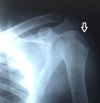

Irreducible shoulder dislocation is an uncommon event. When it does occur, blocks to reduction can include bone, labrum, rotator cuff musculature, or tendon. Concomitant rotator cuff tear at the time of initial dislocation is not an exclusive complication of anterior shoulder dislocation in the older population. Indeed, rotator cuff tear should not be excluded based solely on the patient's age. Rotator cuff interposition is not an uncommon complication after anterior dislocation of the shoulder. It should be suspected when there is incongruency of the joint and persistent subluxation on postreduction radiographs. If such incongruence or subluxation is seen, a computed tomographic (CT) or magnetic resonance imaging (MRI) scan must then be obtained to determine the nature of the interposed soft tissues. The key to treatment is early diagnosis and adequate imaging. Open reduction and repair of the rotator cuff should be performed. We present a technique for treating irreducible anterior shoulder dislocation caused by interposition of the subscapularis tendon. Both CT and MRI observations, along with intraoperative findings and surgical technique, are discussed.